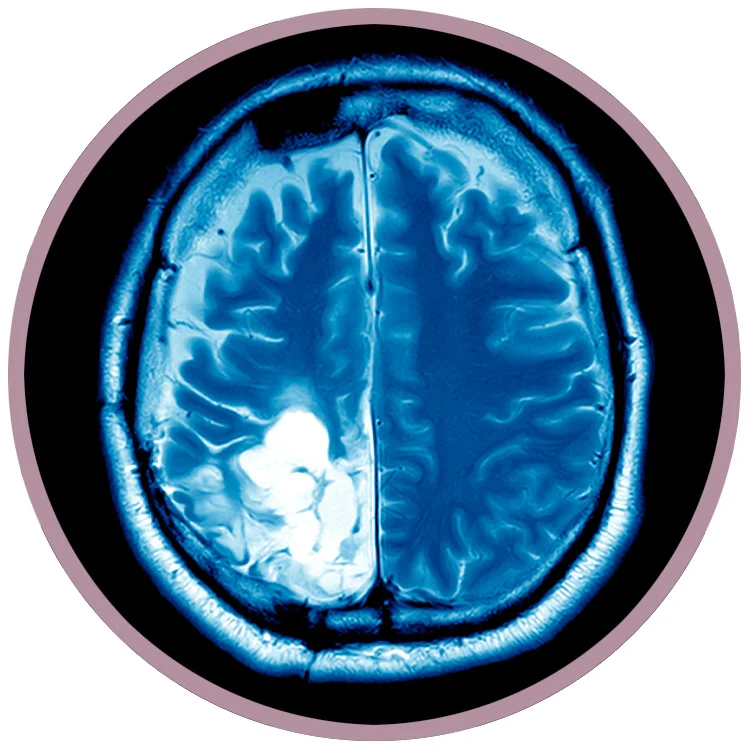

Glioblastoma brain cancer (GBM) is the most dangerous and aggressive form of brain cancer.

GBM is classified as a grade IV astrocytoma.

GBM cells grow rapidly, with large number of cells reproducing at any given time. As a tumor grows, it leads to pressure on the brain, causing symptoms such as headaches, nausea, vomiting, and drowsiness.